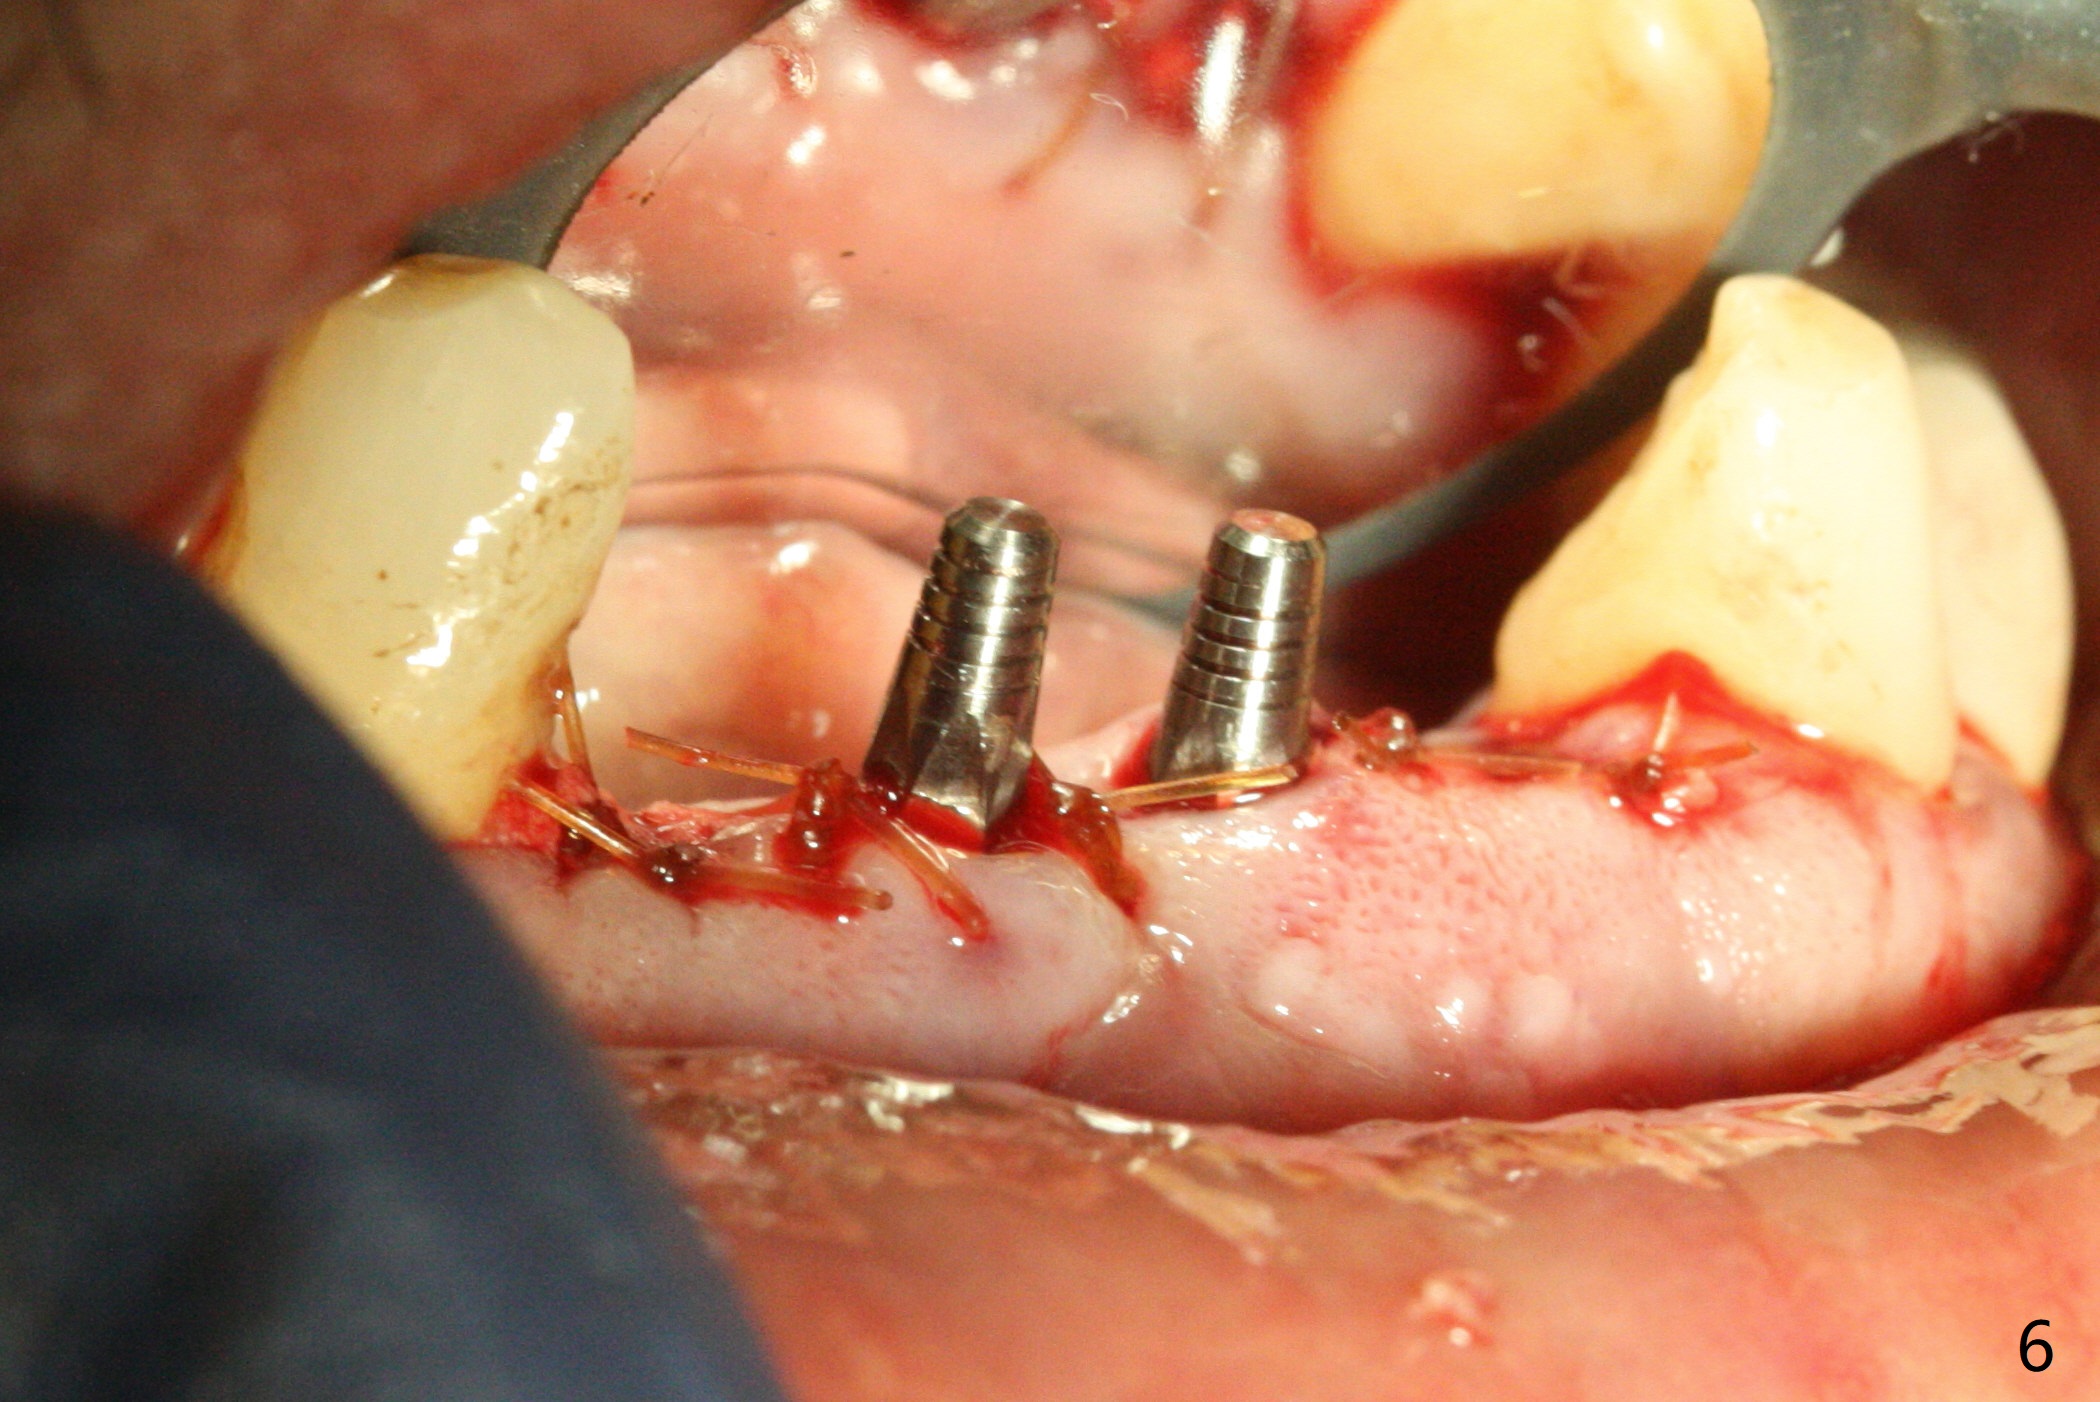

When the patient (smoker) returns for treatment, the apical abscess associated with #25 and 26 reduces with oral Amoxicillin. He agrees with 4 incisor extraction because of 2 apical fistulae (Fig.1 >). Osteotomy starts at the central incisor sockets due to mesial root exposure of the canines (Fig.2 arrowheads) and buccal alveolar bone fracture between #23 and 24 (Fig.7). Two of 3x14(4) mm 1-piece implants are placed with ~ 2 mm buccal gap (Fig.3). After Vanilla graft is placed in the bony defects (Fig.5 *) and Osteogen plug, sutures are placed (Fig.4). The implants are then placed deep to decrease thread exposure (Fig.6). Periodontal dressing is applied instead of provisional. Alveolar bone fracture between #23 and #24 accounts for why an implant is less suitably placed at #24 (Fig.7). Three months postop, composite is added to the pontic areas of the provisional (Fig.8 *). When the provisional is seated, the convex pontics press the used-to-be-flat gingiva (Fig.9 arrows). Thus the concave gingiva forms (Fig.10 *) with corresponding papillae (^). In fact the photos of Fig.8-10 is taken ~3 weeks later. Most of the grafted bone remains in place 3.5 months postop (Fig.11). A piece of floss with 2 knots in one end is placed between the middle units of the final bridge before cementation (Fig.12 (4 months 10 days postop)). In fact removal of residual cement is not so simple. It is tedious (Fig.13,14). An asymptomatic buccal fenetration with implant thread exposure is found 2 months post cementation and persists for another month in spite of advice to reduce smoking (1/2 ppd) and use of water pik (Fig.15). The area will be debrided, followed by bone graft and PRF in a month.